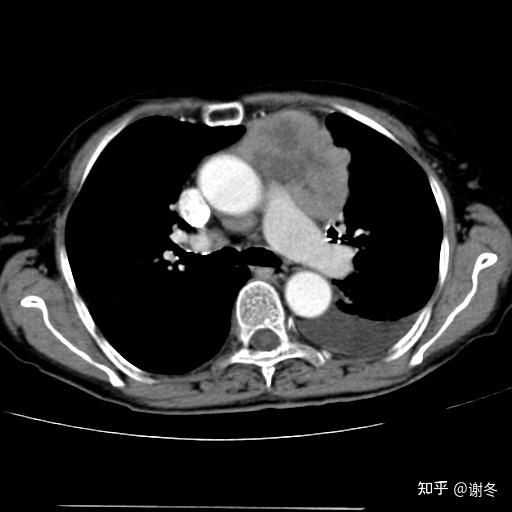

胸腺瘤影像诊断及分期

黄勇老师,胸腺瘤精准影像 (上)

女性,59岁,体检x线发现前上纵膈占位,考虑胸腺瘤,无重症肌无力症状

胸部ct发现胸腺瘤